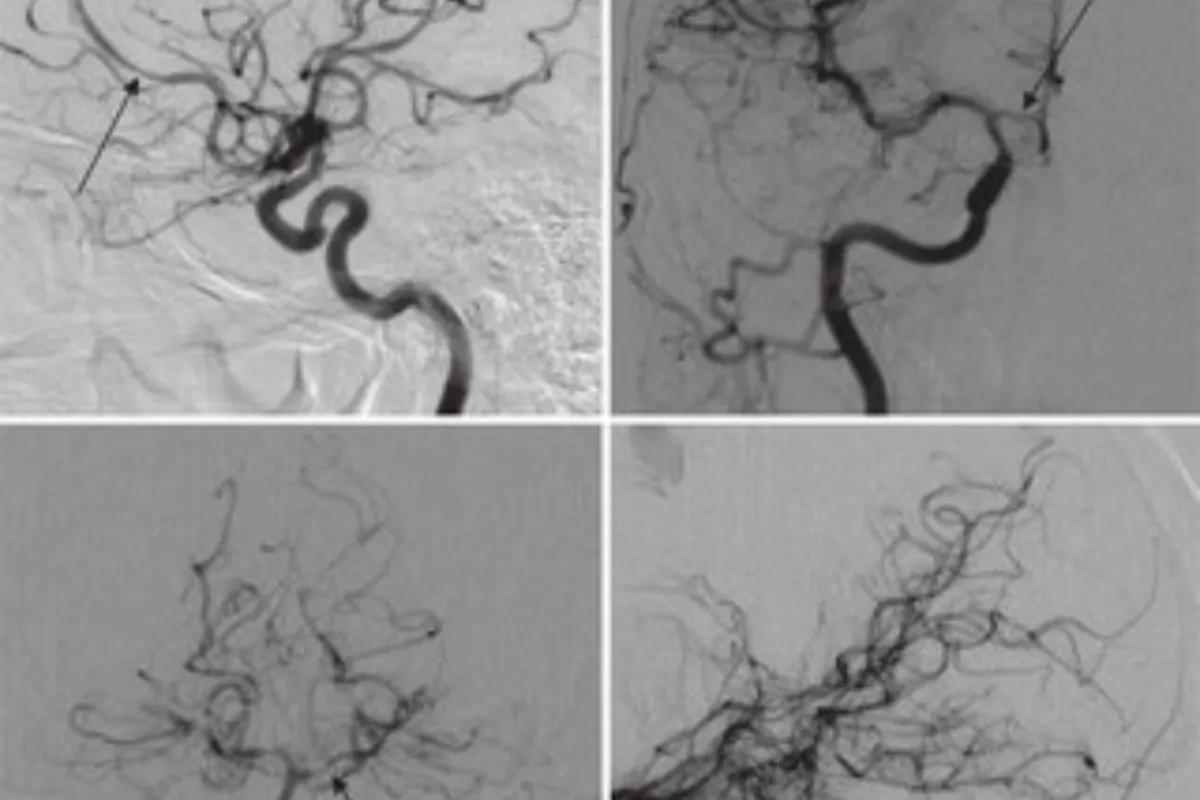

Interventional Radiology (IR) uses real-time imaging such as X-ray, ultrasound, CT, or MRI to guide tiny instruments through the body for treatment — without large surgical incisions.

Common Interventional Radiology Procedures